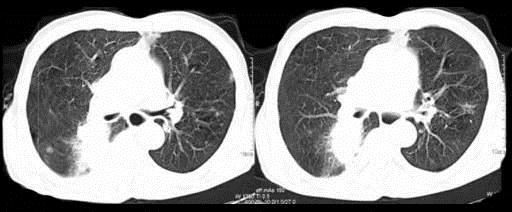

72岁,男,呼吸急促、气喘4个月,请结合胸片,选出最可能的诊断 ( )A.肺癌B.错构瘤C.肺结核D.韦格肉芽肿E.支气管腺瘤

问题 72岁,男,呼吸急促、气喘4个月,请结合胸片,选出最可能的诊断 ( )

选项 A.肺癌 B.错构瘤 C.肺结核 D.韦格肉芽肿 E.支气管腺瘤

答案 A